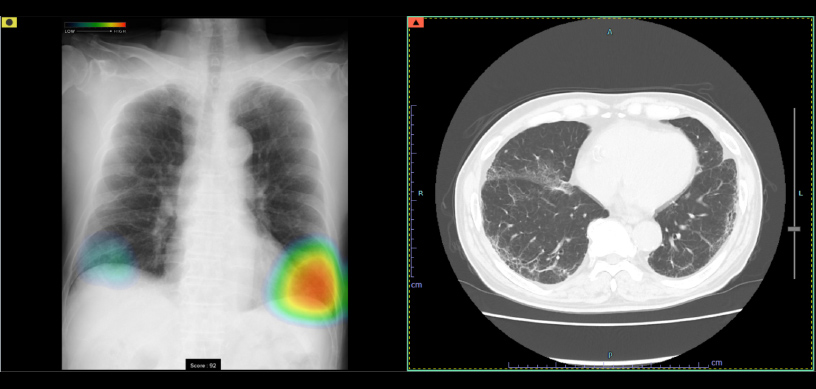

ヒートマップ表示機能

異常が疑われる領域をAIが自動的に解析し、確信度に合わせた表示を行います。確信度のスコアは0~100に分かれており、画像では色分けによるヒートマップとして表示されます。

スコア表示

0~100に分けられた確信度スコアの最大値が数値として表示されます。